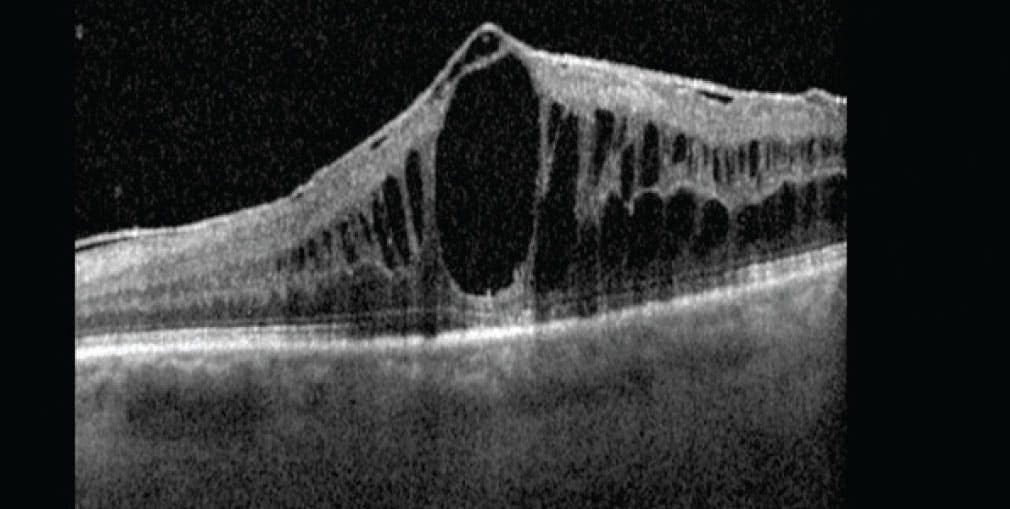

Macular edema is a prevalent complication in uveitis (Figure 2).1 The 7-year follow-up results of the MUST trial revealed that macular edema could be resolved in 94% of patients when treated, although approximately 50% experienced a relapse.25 Similarly, a 12-month follow-up subanalysis of the FAST trial indicated that 50% of patients in both groups showed some persistent macular edema at 12 months.26

<p>Figure 2. This spectral-domain OCT macula scan shows cystoid macular edema.</p>

Figure 2. This spectral-domain OCT macula scan shows cystoid macular edema.